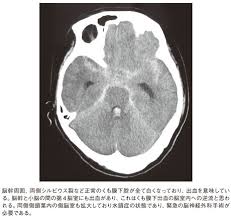

くも膜下出血のctç

くも膜下出血のctç"»åƒã¨è§£å‰– つねぴーblog 内ç§'å°‚æ"»åŒ» from cdn-ak.f.st-hatena.com